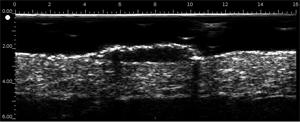

DERMCUP permite la adquisición no invasiva de secciones verticales de la piel in vivo

25 MHz: 16 mm x 12 mm

La dermis es ecogénica. Los ecos provienen de la red de fibras de colágeno y fibras elásticas. En relación a la dermis, las lesiones (tumores, quistes, angiomas …) aparecen como áreas hipoecoicas.

Ultrasonido de alta resolución

Gracias a su frecuencia de 25 MHz y 50 MHz , el DERMCUP ofrece una alta resolución:

Axial: 30 μm

Lateral: 120 μm

En dermatología, es necesario visualizar lesiones infra-centimétricas. Esto no se puede hacer con los escáneres de ultrasonido tradicionales equipados con sondas de 7-13 MHz.

El DERMCUP es adecuado para ver lesiones del tamaño de la décima de milímetro.